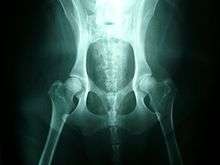

The classic diagnostic technique is with appropriate X-rays and hip scoring tests. These should be done at an appropriate age, and perhaps repeated at adulthood - if done too young they will not show anything. Since the condition is to a large degree inherited, the hip scores of parents should be professionally checked before buying a pup, and the hip scores of dogs should be checked before relying upon them for breeding. Despite the fact that the condition is inherited, it can occasionally arise even to animals with impeccably hip scored parents.

In diagnosing suspected dysplasia, the x-ray to evaluate the internal state of the joints is usually combined with a study of the animal and how it moves, to confirm whether its quality of life is being affected. Evidence of lameness or abnormal hip or spine use, difficulty or reduced movement when running or navigating steps, are all evidence of a problem. Both aspects have to be taken into account since there can be serious pain with little X-ray evidence.

It is also common to X-ray the spine and legs, as well as the hips, where dysplasia is suspected, since soft tissues can be affected by the extra strain of a dysplastic hip, or there may be other undetected factors such as neurological issues (e.g. nerve damage) involved.

Dogs might exhibit signs of stiffness or soreness after rising from rest, reluctance to exercise, bunny-hopping or other abnormal gait (legs move more together when running rather than swinging alternately), lameness, pain, reluctance to stand on rear legs, jump up, or climb stairs, subluxation or dislocation of the hip joint, or wasting away of the muscle mass in the hip area. Radiographs (X-rays) often confirm the presence of hip dysplasia, but radiographic features may not be present until two years of age in some dogs. Moreover, many affected dogs do not show clinical signs, but some dogs manifest the problem before seven months of age, while others do not show it until well into adulthood.